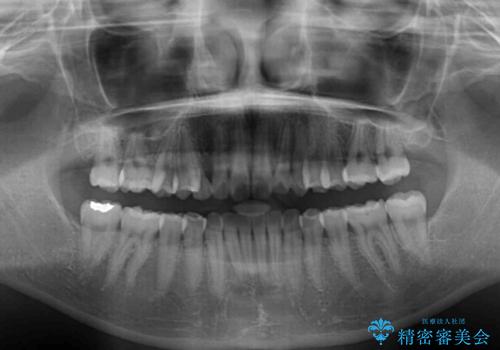

- 前歯のクロスバイトや残存している乳歯を気にして来院された患者様です。

上顎骨の幅が下顎骨よりも小さいので、拡大装置により骨幅を広げて上下関係を改善し、その後インビザラインにて歯並びを整えることとしました。

上下の骨幅を改善したことで、スムーズに歯列矯正を行うことができました。